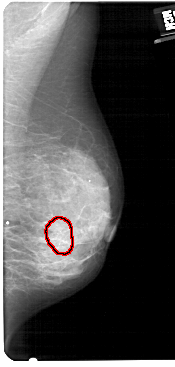

A_1431_1.RIGHT_MLO

RIGHT_MLO LINES 5491 PIXELS_PER_LINE 2611 BITS_PER_PIXEL 12 RESOLUTION 43.5 OVERLAY

FILE: A_1431_1.RIGHT_MLO.OVERLAY

TOTAL_ABNORMALITIES 1

ABNORMALITY 1

LESION_TYPE CALCIFICATION TYPE AMORPHOUS DISTRIBUTION CLUSTERED

ASSESSMENT 4

SUBTLETY 3

PATHOLOGY BENIGN

TOTAL_OUTLINES 1

BOUNDARY